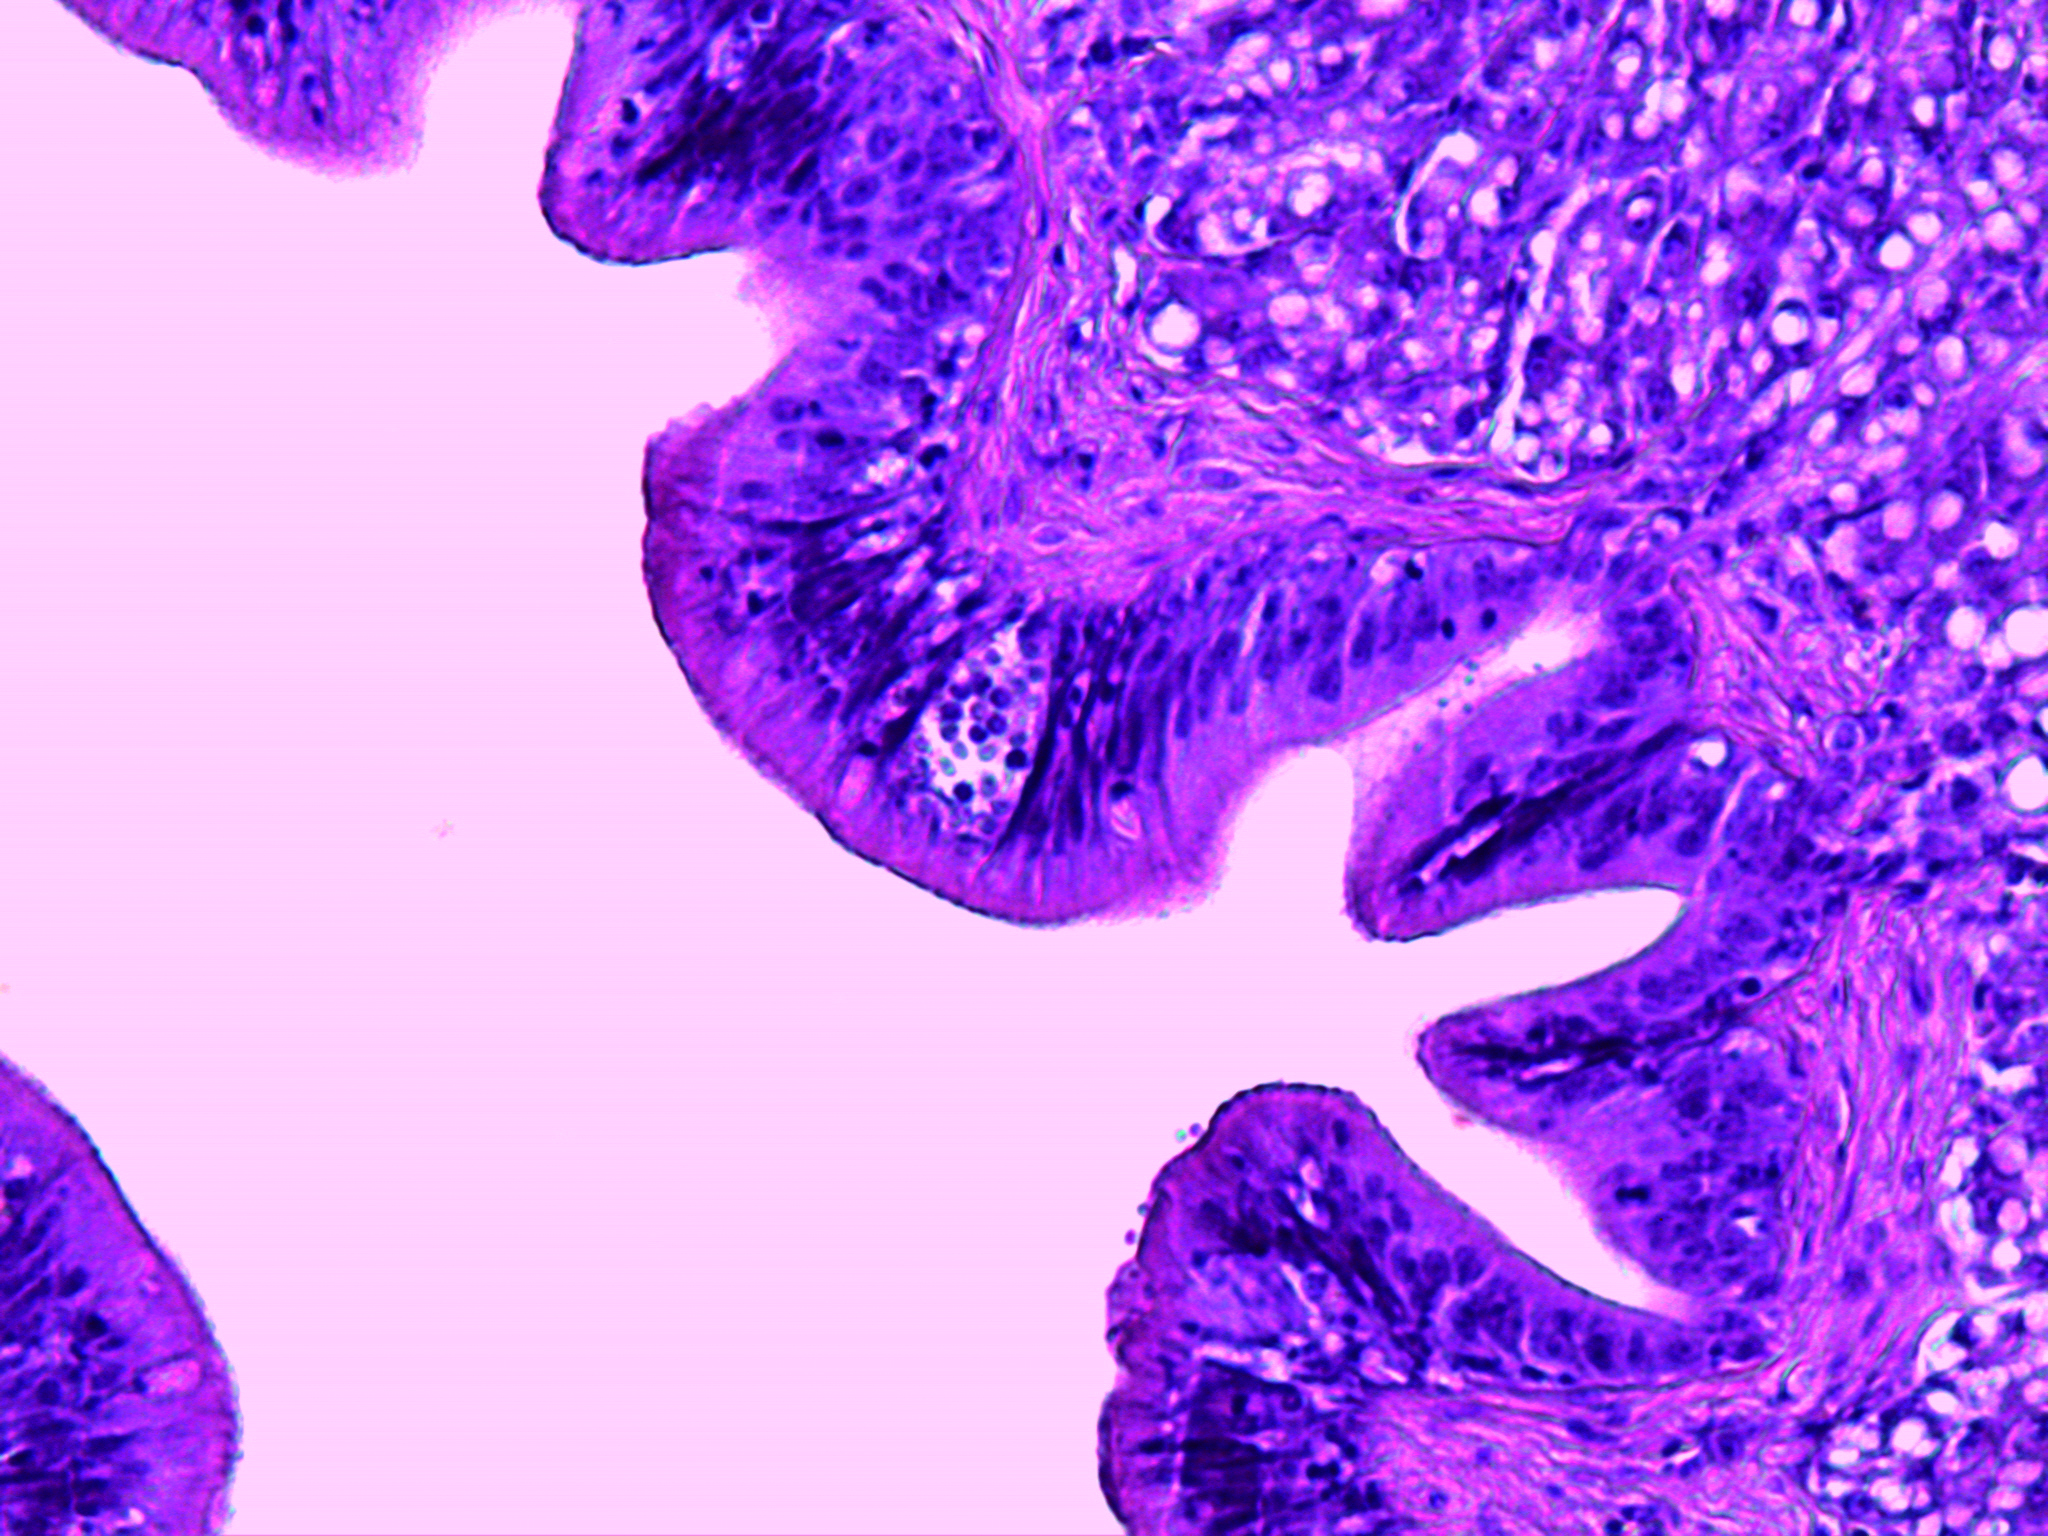

Enteromixosi

Agente: Enteromyxum leei (Myxidiidae, parassita istozoico dei mixozoi).

Sintomi: Questo parassita mixosporeo infetta la mucosa intestinale dell'orata causando una grave perdita di peso e un'elevata mortalità. La spigola può fungere da vettore senza essere influenzata. La trasmissione orizzontale avviene tra i pesci attraverso forme pre-sporogoniche espulse in pacchetti fecali, piuttosto che spore tipiche di altri mixosporei. Le spore mature hanno una caratteristica forma a "croissant" con capsule polari alle estremità.

Controllo: Nessun trattamento. La prevenzione consiste nella separazione di pesci di diverse dimensioni per ridurre la trasmissione, la pulizia delle reti e la rimozione della mortalità.